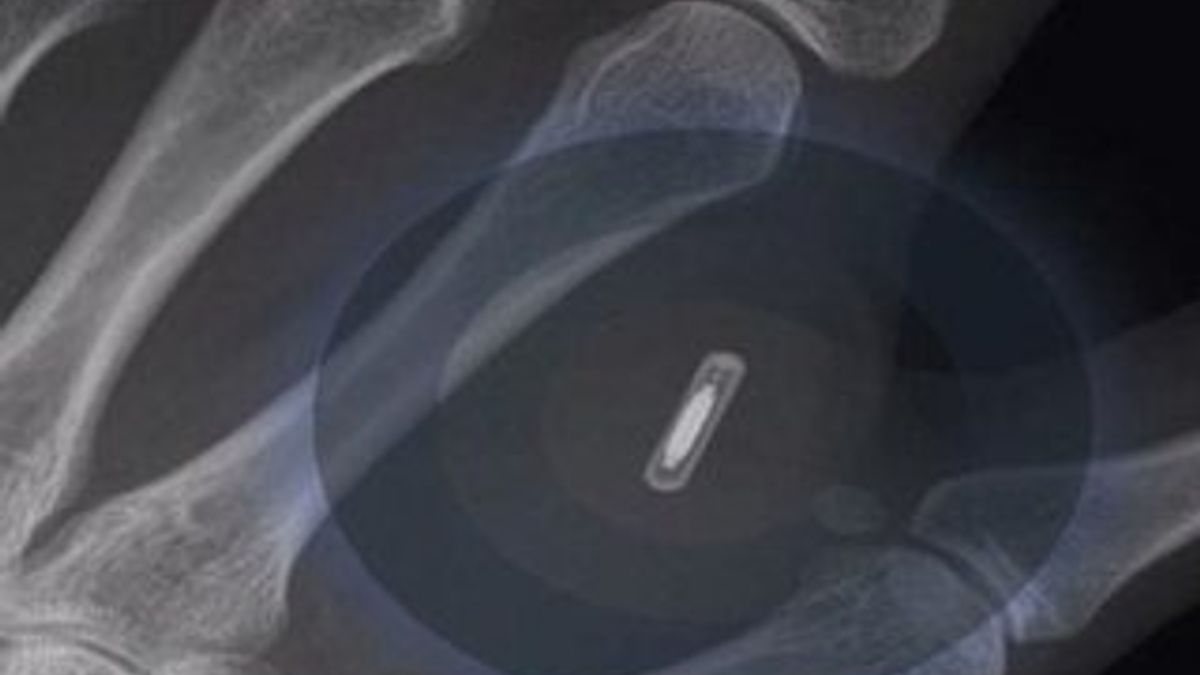

Avustralya’nın Brisbane kentinde yaşayan Ben Slater, eline taktırdığı mikroçip sayesinde elinin bir hareketiyle kapıları ve ışıkları açıp kapatmayı başardı. Slater, bir dövmecide eline yerleştirilen pirinç tanesi büyüklüğündeki mikroçip sayesinde, yeni iPhone 6 ile de ‘ iletişim kurmayı’ hedefliyor.

Tüm dünyada merakla beklenen iPhone 6, Apple tarafından yarın piyasaya sürülecek. Reklam direktörü Slater, Daily Mail Avustralya’ya, geleceğin teknolojilerinin daima ilgisini çektiğini söyledi. Slater, Apple’ın yeni akıllı telefonunun elinde yerleştirdiği çipi de okuyabileceğini düşünüyor. İnsana mikroçip uygulaması Avustralya için yeni olsa da ABD’de 2004 yılından beri hızla yaygınlaşıyor. Mikroçiplerde kronik hastalığı olan kişilerin sağlık bilgileri tutuluyor.